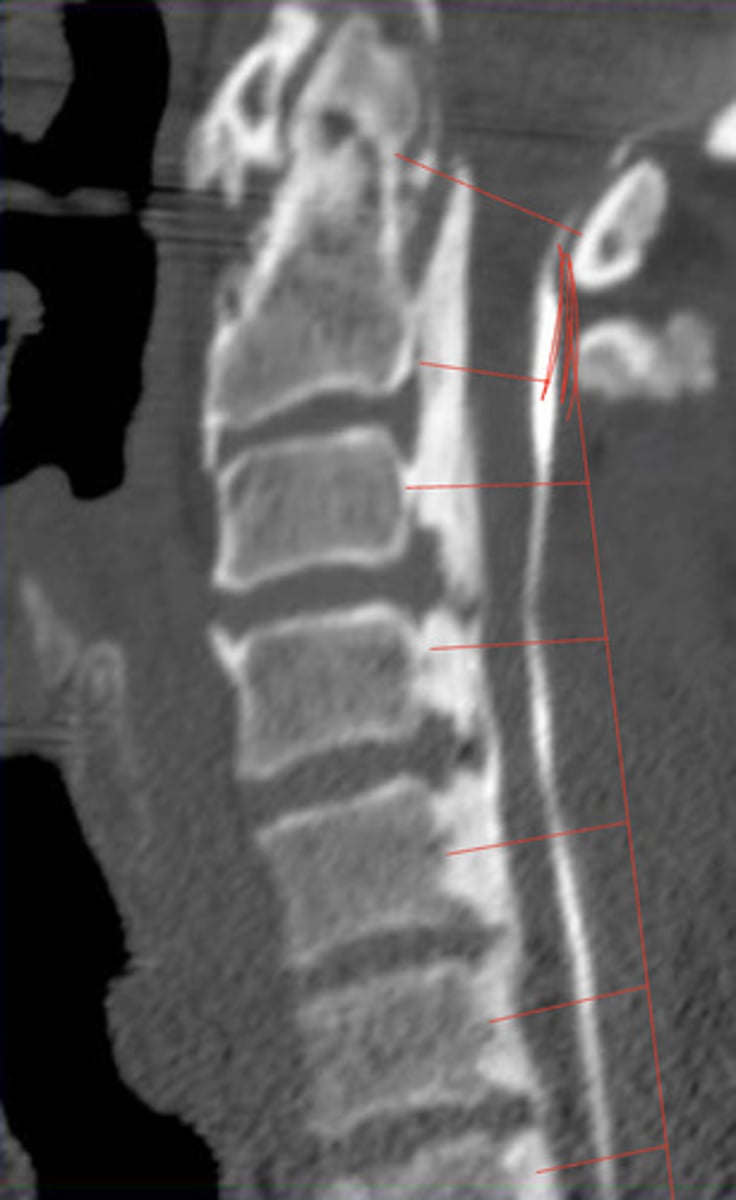

CT

What has the best image of cortical bone?

DISH (mid body to mid body)

What is the arrow pointing at?

Mid body

Where does the ALL attach to the vertebrae?

DISH (mid body flow of the anterior vertebral line)

What is wrong with this image?

Calcification of ALL or DISH

What is the pathology?

16, 14, 13, 12, 12, 12

What is the lateral sagittal canal size for each cervical

Back of dens to spinolamina line

How do you measure the lateral sagittal canal size of c1?